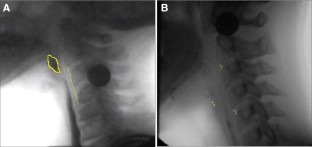

Fig. 1

Fig. 2